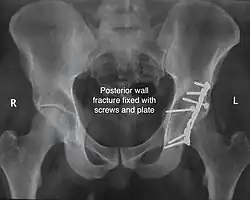

Posterior wall fracture fixed with screws and plate -

The final management depends on the size of the fragment(s), stability and congruence of the joint. In some cases traction for six to eight weeks may be the only treatment required; however, surgical fixation using screw(s) and plate(s) may be required if the injury is more complex. The latter treatment will be called for if bone fragments do not fall into place, or if they are found in the joint, or if the joint itself is unstable.

Implants : normally lag screws and reconstruction plates are preferred implants